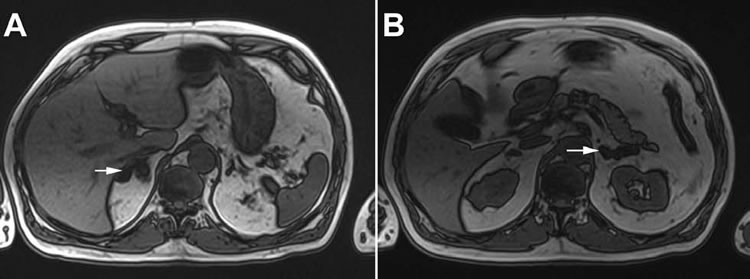

Por litiasis renal, se realizó Pielo-TAC que, además de litiasis calicilar y ureteral derecha, mostró nódulos suprarrenales bilaterales. La densitometría ósea certificó osteopenia moderada de ambas caderas (T score -1.4). Una resonancia magnética de abdomen confirmó el engrosamiento polinodular de ambas glándulas suprarrenales, con un nódulo predominante de 2 cm a derecha. La imagen radiológica era compatible con hiperplasia suprarrenal macronodular (Figura 1). Con la sospecha de SC se midió cortisol libre urinario de 24 horas (CLU) que fue 48.2 ug/24 h (VN<90) y cortisol plasmático 9 am: 22.4 ug/dL. La dosis nocturna de 1 mg de dexametasona no suprimió el cortisol matinal (8.2 ug/dL), pero se constató mantención del ritmo circadiano de cortisol (09 h: 12.4 ug/dL, 16 h: 7.6 ug/dL, 23 h: 5.2 ug/dL).

Es de gran trascendencia la identificación de los receptores hormonales aberrantes en la glándulas suprarrenales de pacientes con hiperplasia e hiperproductores de cortisol, ya que ello, hoy en día, puede abrir la oportunidad para tratamientos específicos como alternativa a la adrenalectomía, usando moléculas que inhiban la producción del ligando endógeno o antagonicen al receptor. En esta línea y según el tipo de receptor involucrado, se han probado distintos tratamientos, como octreotide para bloquear la liberación postprandial de GIP, bloqueadores del receptor adrenérgico ß y AII, acetato de leuprolide para bloquear la secreción de LH y antagonistas del receptor de vasopresina tipo 11,12. Sin embargo, pese a la disminución de secreción de cortisol, no han mostrado eficacia clínica mantenida ni regresión del tamaño tumoral, Figura 1. RM con crecimiento polinodular de ambas glándulas suprarrenales (flechas) al momento del diagnóstico de HSMIA (A. derecha y B. izquierda). La RM de control, un año después de la suprarrenalectomía derecha, no mostró variación de la suprarrenal izquierda. siendo posible que existan otros mecanismos genéticos o vías involucradas en la proliferación celular.